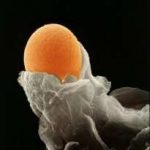

第三代试管婴儿会在胚胎培养完成后对胚胎进行检测,其目的是在移植过程中尽可能避免染色体异常的胚胎,降低流产的可能性和移植成功后胎儿畸形的概率。